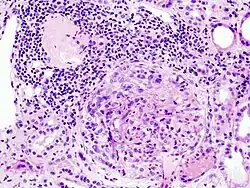

| Histopathological image of crescentic glomerulonephritis in a patient with MPO-ANCA positive rapid progressive glomerulonephritis. Hematoxylin & eosin stain. | |

Rapidly progressive glomerulonephritis (RPGN) is a syndrome of the kidney that is characterized by a rapid loss of kidney function,[4][5] (usually a 50% decline in the glomerular filtration rate (GFR) within 3 months)[5] with glomerular crescent formation seen in at least 50%[5] or 75%[4] of glomeruli seen on kidney biopsies. If left untreated, it rapidly progresses into acute kidney failure[6] and death within months. In 50% of cases, RPGN is associated with an underlying disease such as Goodpasture syndrome, systemic lupus erythematosus or granulomatosis with polyangiitis; the remaining cases are idiopathic. Regardless of the underlying cause, RPGN involves severe injury to the kidneys' glomeruli, with many of the glomeruli containing characteristic glomerular crescents (crescent-shaped scars).[7]

It is thought that antineutrophil cytoplasmic antibodies (ANCA) interact with antigens in the cytoplasm of neutrophils to cause an early degranulation, triggering the release of lytic enzymes at the site of injury[8] and leading to the formation of glomerular crescents that consist primarily of parietal epithelial cells from Bowman's capsule and in some cases podocytes.[9]